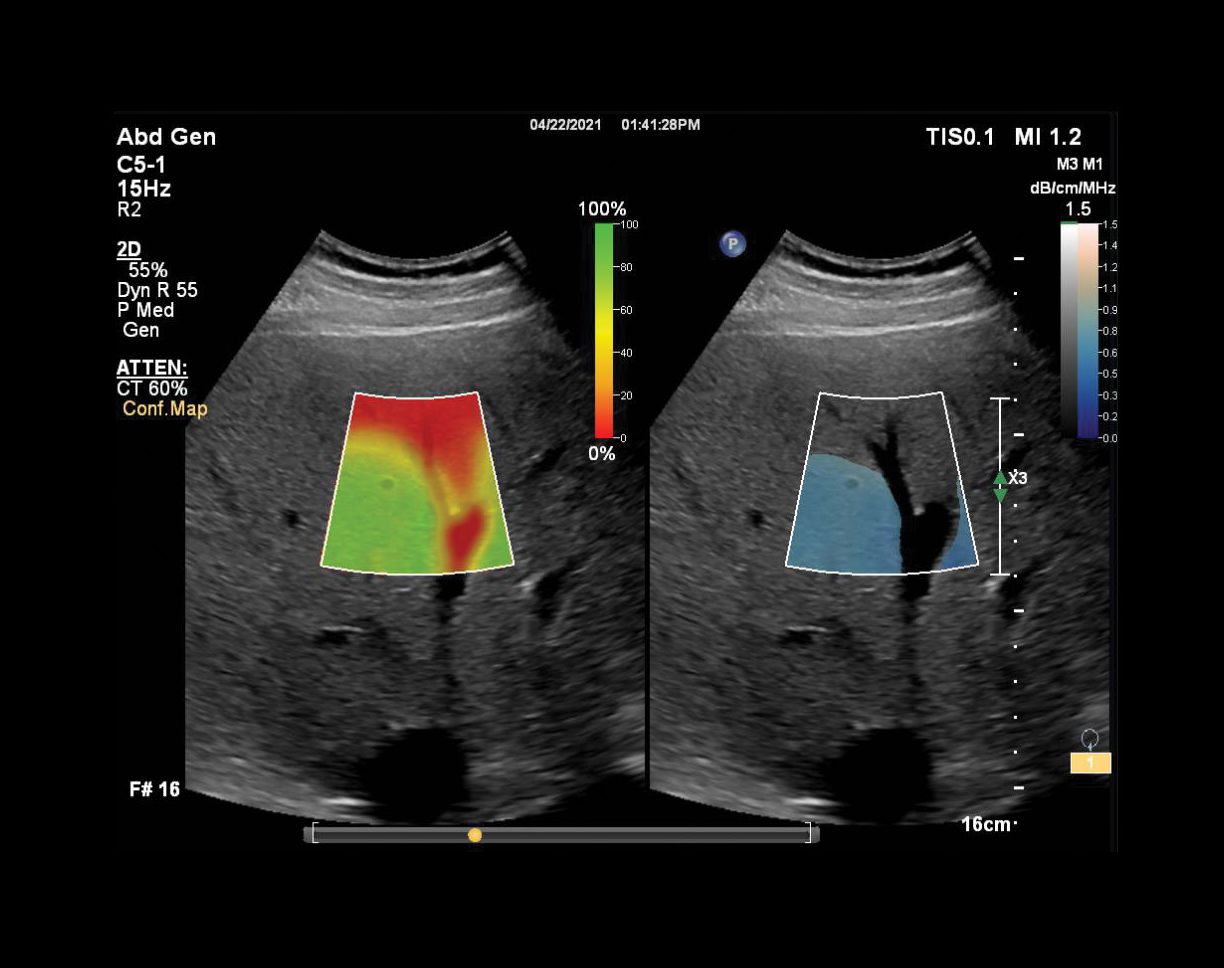

Attenuation confidence map

The LFQ solution also includes a hepatorenal index (HRI) tool, which measures the ratio of echo amplitude between the liver and kidney. HRI has been used clinically for fatty liver detection and can be calculated using ultrasound images.